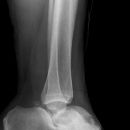

Totale Talusluxation